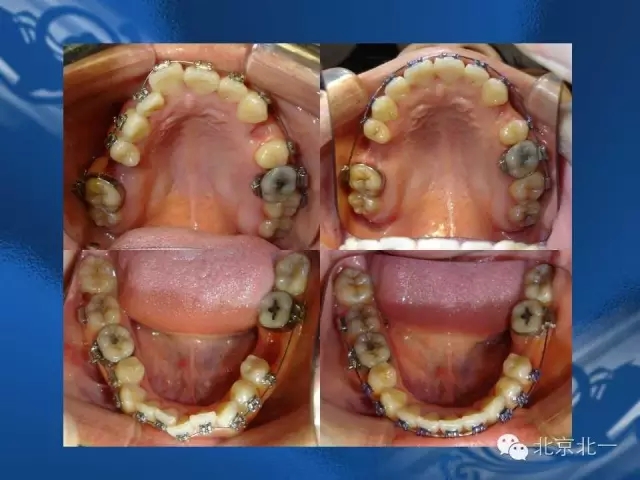

走進正畸固定矯治技術